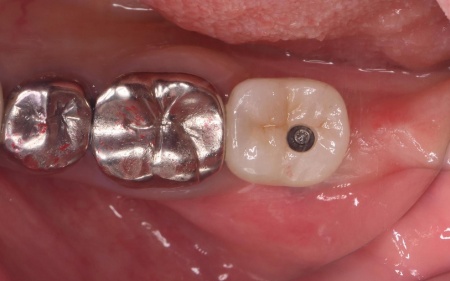

治療後

| 行ったご提案・治療内容 | まずは左下奥歯に装着されていた被せ物を慎重に除去し、歯根の状態を直接確認します。 その結果、歯根破折が明確に認められたため、歯の温存は困難であると判断しました。 抜歯後の治療として、以下2種類の方法を提案しました。 ①延長ブリッジ ②インプラント それぞれのメリットとデメリットを丁寧にお伝えしたところ、患者様は②のインプラント治療を選択されました。 まずは局所麻酔を行い、破折した歯を丁寧に抜きます。 抜歯後は骨の治癒を待つため、約3ヶ月間の経過観察を行いました。 経過観察後、骨の状態が安定したことを確認したら、インプラント体(人工歯根)を顎の骨に埋め込む手術を行います。 手術では、歯茎を切開した骨を露出させ、専用の器具で慎重に穴を形成したうえでインプラント体を埋入します。続いて歯茎を縫合し、インプラント体が骨と結合するまでの期間を設けました。 後日、インプラント体と骨がしっかりと結合したタイミングで、インプラント体の上に土台を装着し、人工の歯を取り付けます。 最後に、装着したインプラントの見た目や使用感、噛む機能の回復などを確認して、治療を終了しています。 |